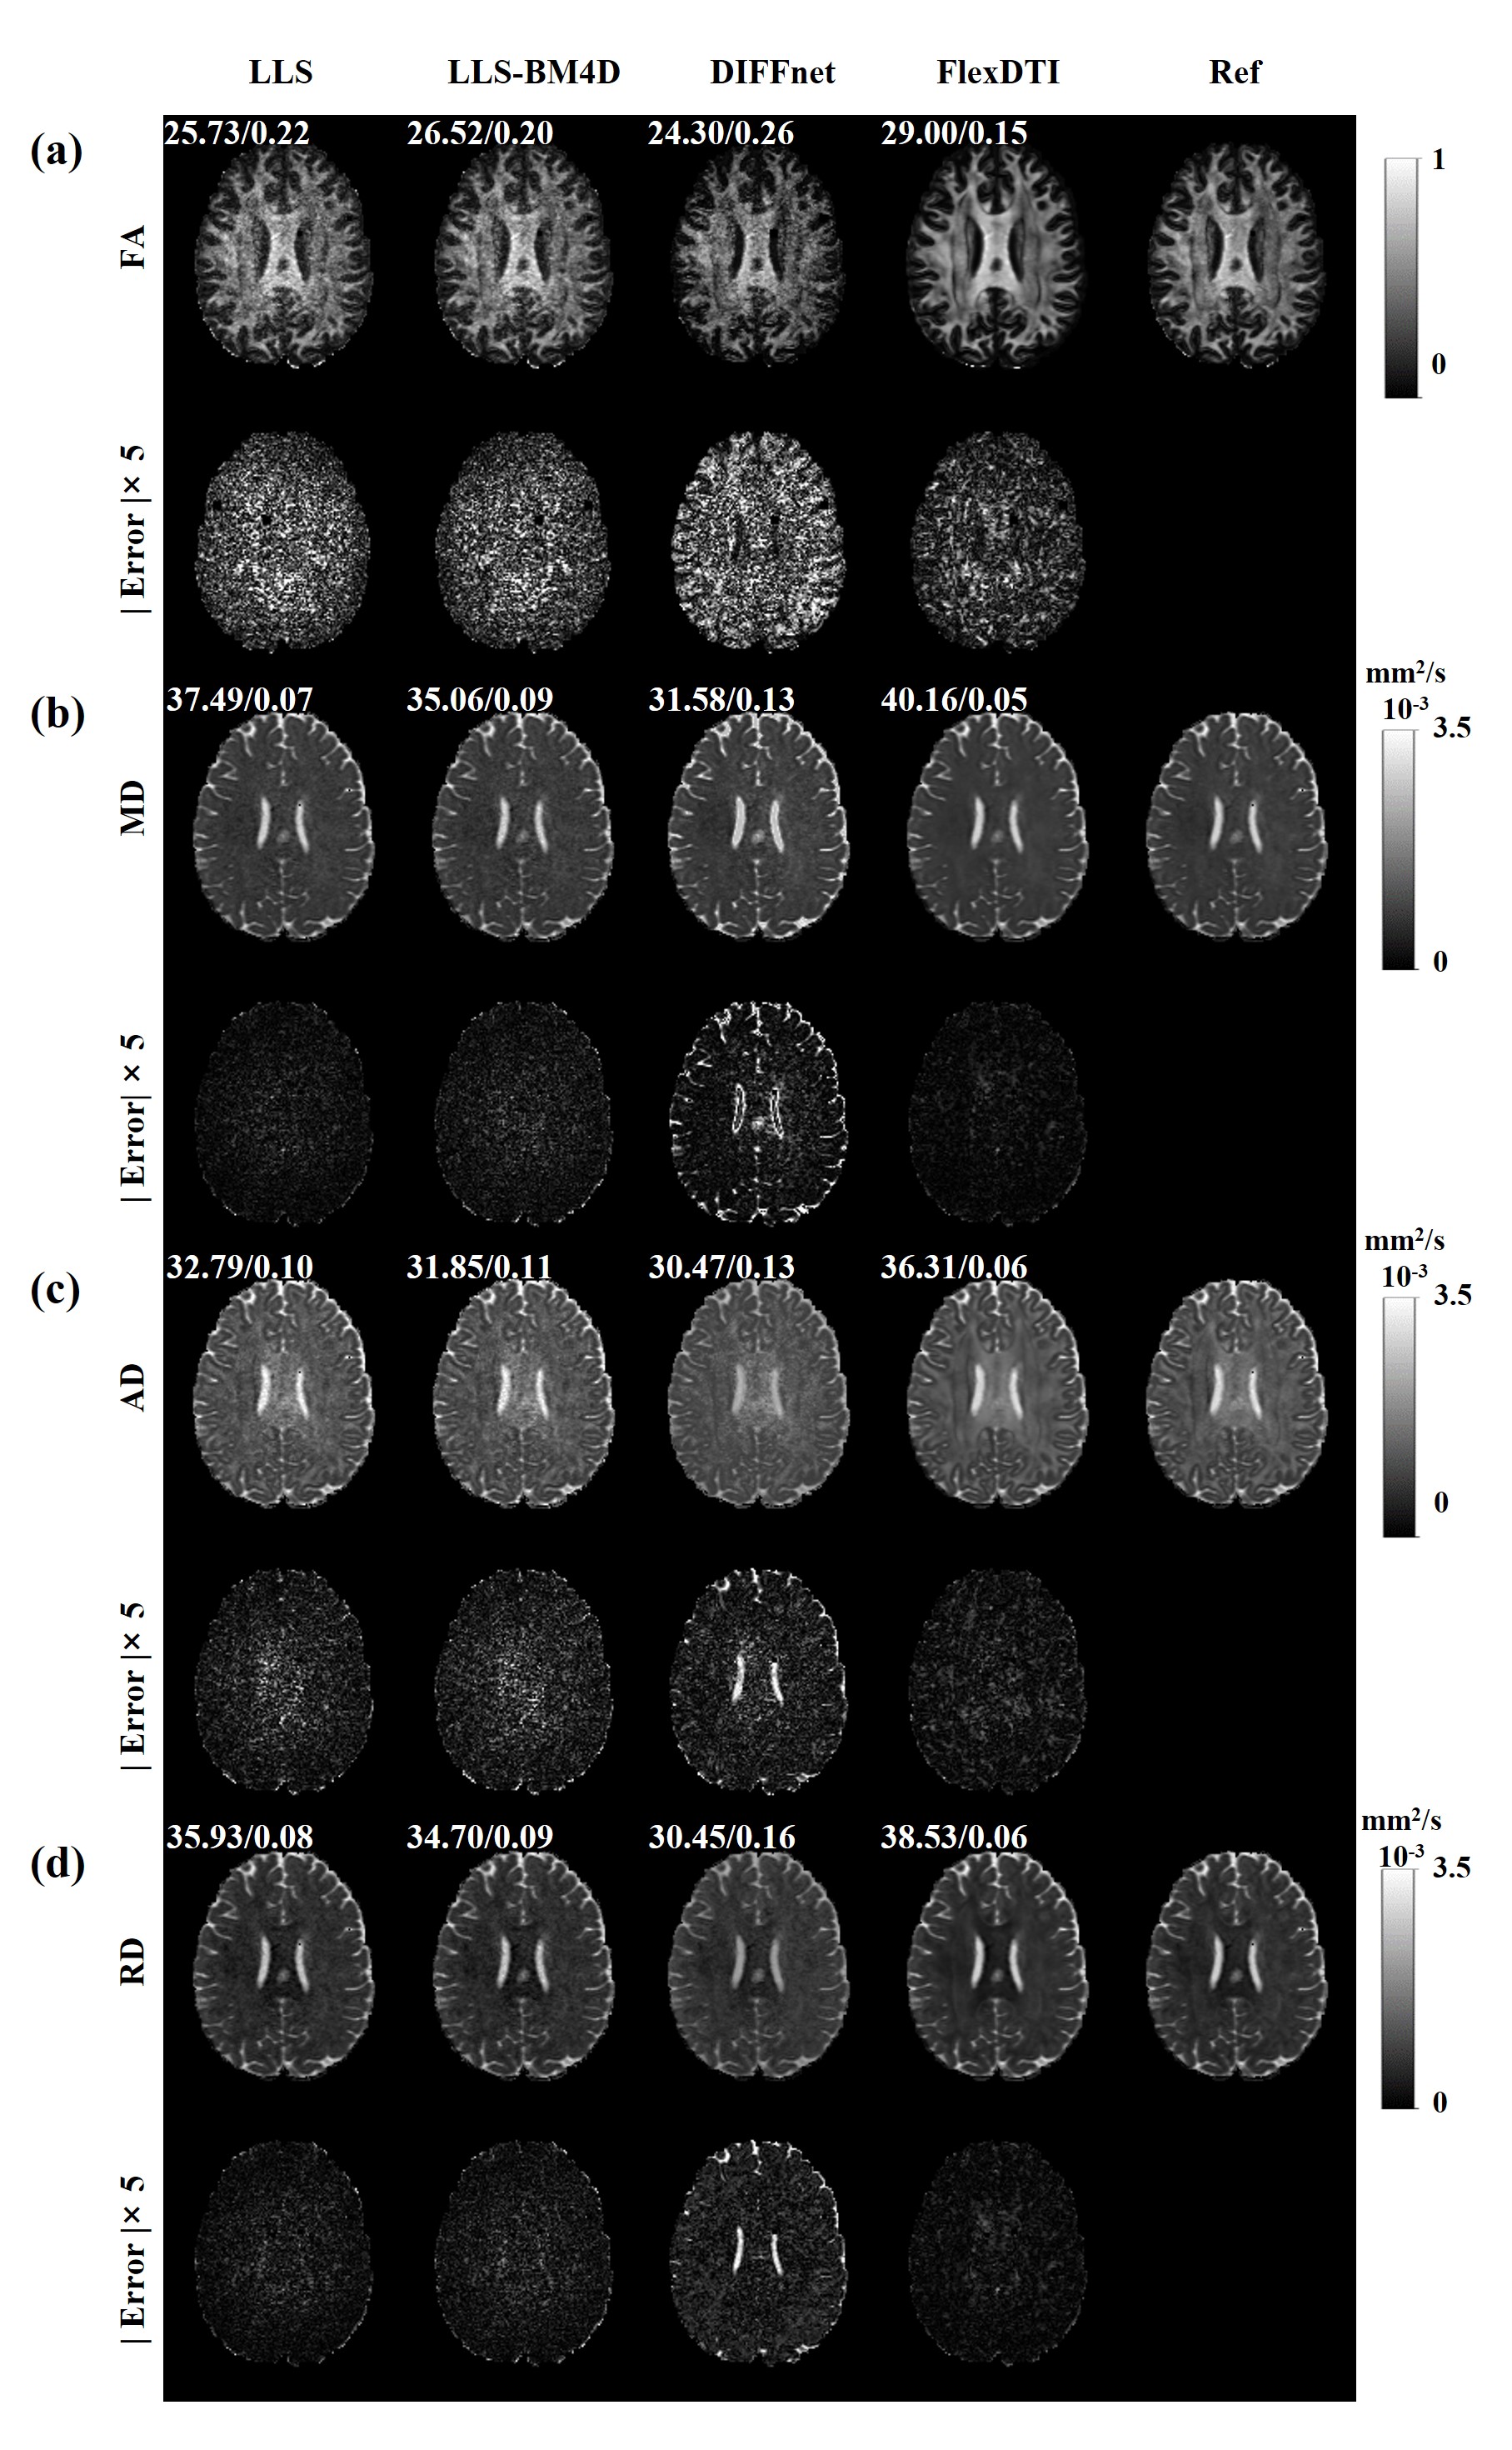

In Figure 3, 12 DW images with flexible diffusion gradient directions were used. Similar to the results with 6 DW images, FlexDTI has significant performance improvement compared to the other methods. Table 2 presents the mean ± standard deviation of PSNR, SSIM and NRMSE. Compared to DIFFnet, FlexDTI reduces NRMSE by 0.15, increases PSNR by 4.12 dB and SSIM by 0.05 on FA, and reduces NRMSE by 0.13, increases PSNR by 8.85 dB and SSIM by 0.02 on MD.

Figure 3: Four parametric maps (FA, MD, AD and RD) reconstructed by LLS, LLS-BM4D, DIFFnet and FlexDTI using 12 DW images with flexible diffusion gradient directions. The references were reconstructed by LLS using 90 DW images. The PSNRs and NRMSEs are given at the upper left corner of each reconstruction image.

Table 2: Quantitative assessment of FA, MD, AD and RD obtained with different methods using 12 DW images from HCP dataset.

DTI parametric map Metrics LLS LLS-BM4D DIFFnet FlexDTI

FA PSNR (dB) 25.40 ± 2.85 26.28 ± 2.88 25.35 ± 2.03 29.47 ± 1.94

SSIM 0.91 ± 0.05 0.91 ± 0.05 0.89 ± 0.05 0.94 ± 0.03

NRMSE 0.43 ± 0.23 0.39 ± 0.22 0.41 ± 0.16 0.26 ± 0.13

MD PSNR (dB) 37.76 ± 2.89 35.62 ± 2.48 30.62 ± 2.34 39.47 ± 1.34

SSIM 0.97 ± 0.02 0.96 ± 0.02 0.96 ± 0.02 0.98 ± 0.01

NRMSE 0.09 ± 0.04 0.13 ± 0.21 0.20 ± 0.03 0.07 ± 0.04

AD PSNR (dB) 32.88 ± 2.70 32.18 ± 2.52 29.58 ± 2.02 36.88 ± 1.81

SSIM 0.95 ± 0.02 0.95 ± 0.03 0.94 ± 0.03 0.97 ± 0.01

NRMSE 0.14 ± 0.05 0.16 ± 0.09 0.20 ± 0.03 0.09 ± 0.03

RD PSNR (dB) 36.47 ± 3.00 35.35 ± 2.58 29.97 ± 2.18 38.53 ± 1.25

SSIM 0.96 ± 0.02 0.96 ± 0.02 0.95 ± 0.02 0.98 ± 0.01

NRMSE 0.11 ± 0.05 0.14 ± 0.02 0.22 ± 0.03 0.09 ± 0.07